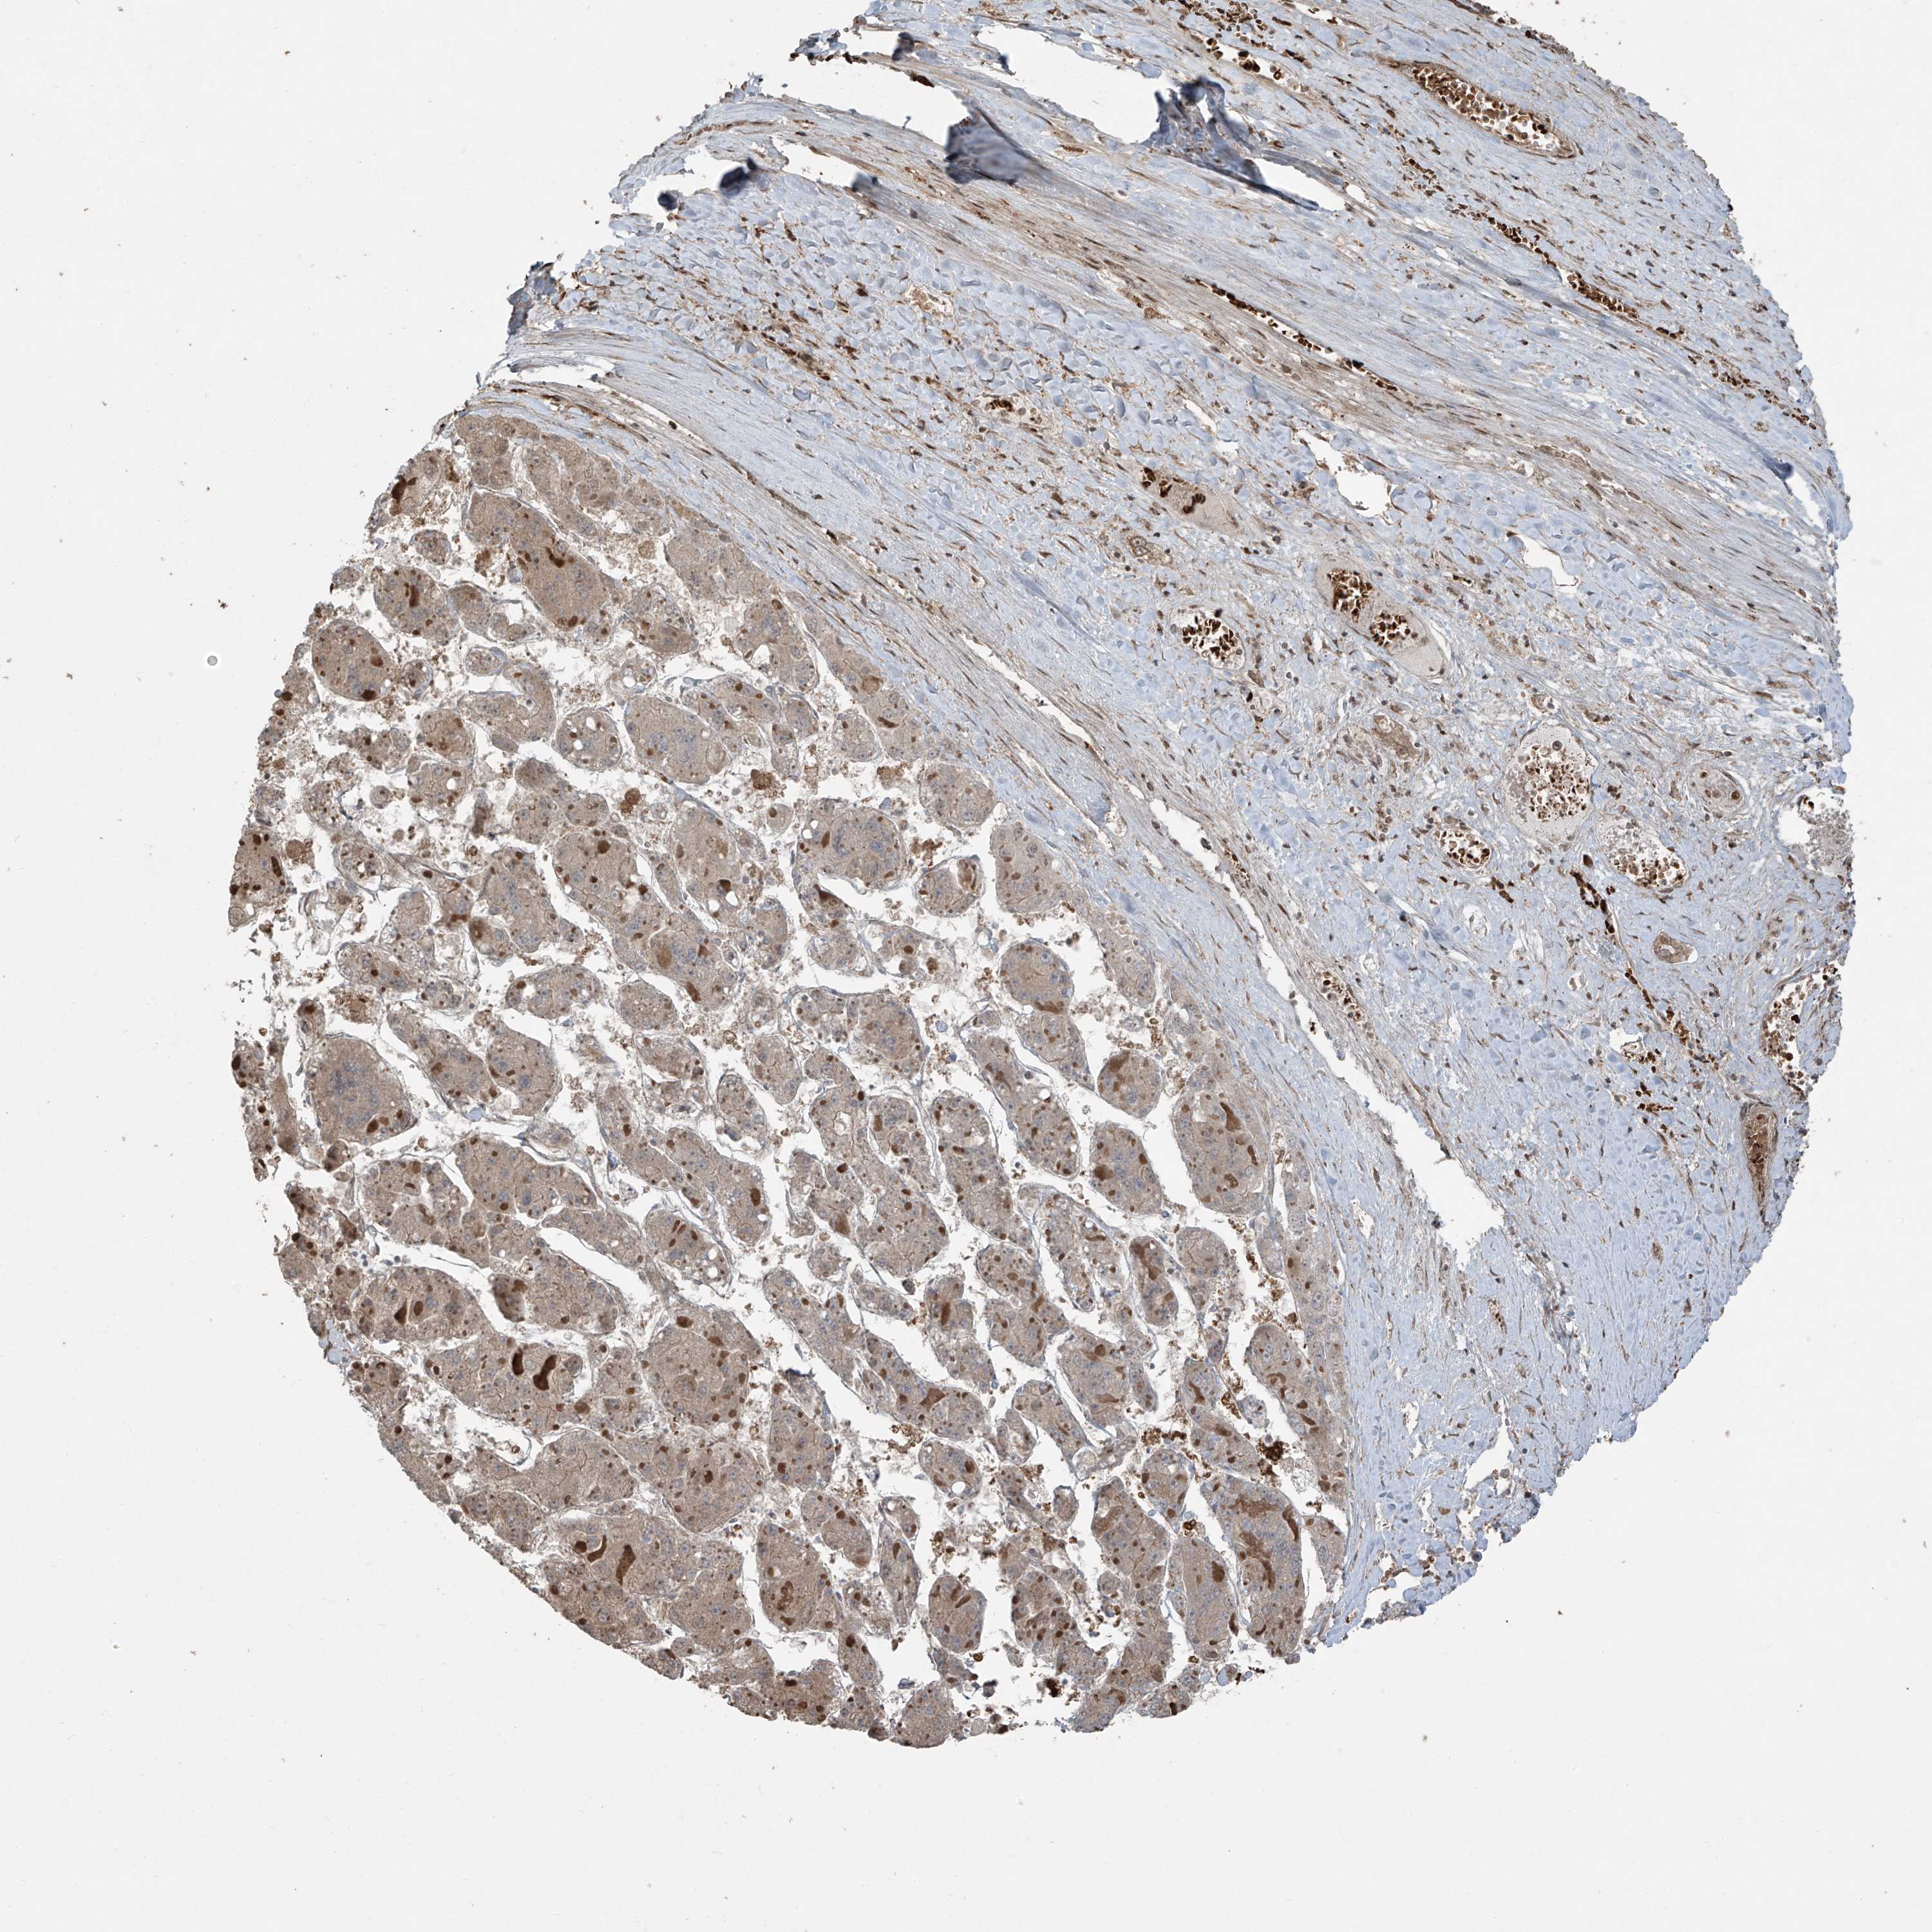

LIVER CANCER - Protein expressioni

A mouse-over function shows sample information and annotation data. Click on an image to view it in a full screen mode. Samples can be filtered based on level of antibody staining by selecting one or several of the following categories: high, medium, low and not detected. The assay and annotation is described here.

Note that samples used for immunohistochemistry by the Human Protein Atlas do not correspond to samples in the TCGA dataset.

Antibody stainingi

Antibody staining in the annotated cell types in the current human tissue is reported as not detected, low, medium, or high, based on conventional immunohistochemistry profiling in selected tissues. This score is based on the combination of the staining intensity and fraction of stained cells.

Each image is clickable and will lead to virtual microscopy that enables deeper exploration of all samples and also displays staining intensity scores, fraction scores and subcellular localization as well as patient and tissue information for each sample.

Antibody HPA035072

Staining

High

Medium

Low

Not detected

Intensity

Strong

Moderate

Weak

Negative

Quantity

>75%

75%-25%

<25%

None

Location

Nuclear

Cytoplasmic/membranous

Cytoplasmic/membranous,nuclear

Cholangiocarcinoma

Carcinoma, Hepatocellular, NOS